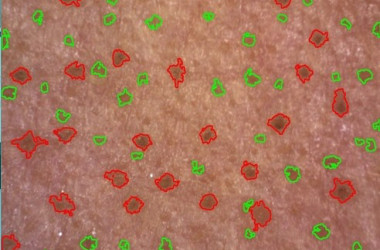

- Kamera za kožo Visioscope® PC 35

Opremljeno z vzporedno in navzkrižno polarizirano svetlobo:

- Vzporedno polarizirana svetloba vizualizira površinsko strukturo kože

- Navzkrižno polarizirana svetloba razkriva globlje plasti kože, kot so pigmentacija in vaskularne strukture

Načine osvetlitve lahko takoj spremenite s pritiskom na gumb kamere. Na podlagi zajetih slik programska oprema izvede enostavno in objektivno analizo slik gub, por in pigmentnih madežev. Popeljite svoje stranke na vizualno potovanje po obrazu in telesu.

- Kvantitativna analiza s posebnimi trakovi

Trakovi Sebufix® in Corneofix®, dobavljeni v praktičnih podajalnikih, se uporabljajo v kombinaciji s kamero Visioscope® za zagotavljanje jasnih vizualnih rezultatov nastajanja sebuma in luščenja kože, ki jih je strankam enostavno razložiti.

Sebufix® F 16 prikazuje nastajanje sebuma v realnem času

Corneofix® F 20 omogoča podrobno analizo deskvamacije in suhosti.